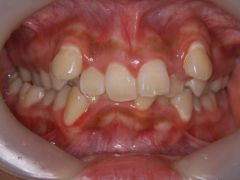

初診時年齢17歳の女子 上下顎前歯の著しい叢生を主訴に来院された。

大臼歯関係は上顎が下顎より前方にあり、叢生に加え上下の歯の咬合関係にも大きなずれがあった。顎外固定装置(ヘッドギア)を併用し上下顎マルチブラケット装置を使用して、上下顎小臼歯を抜歯していただき動的治療を行った。 動的治療期間2年3か月間(調整来院25回)